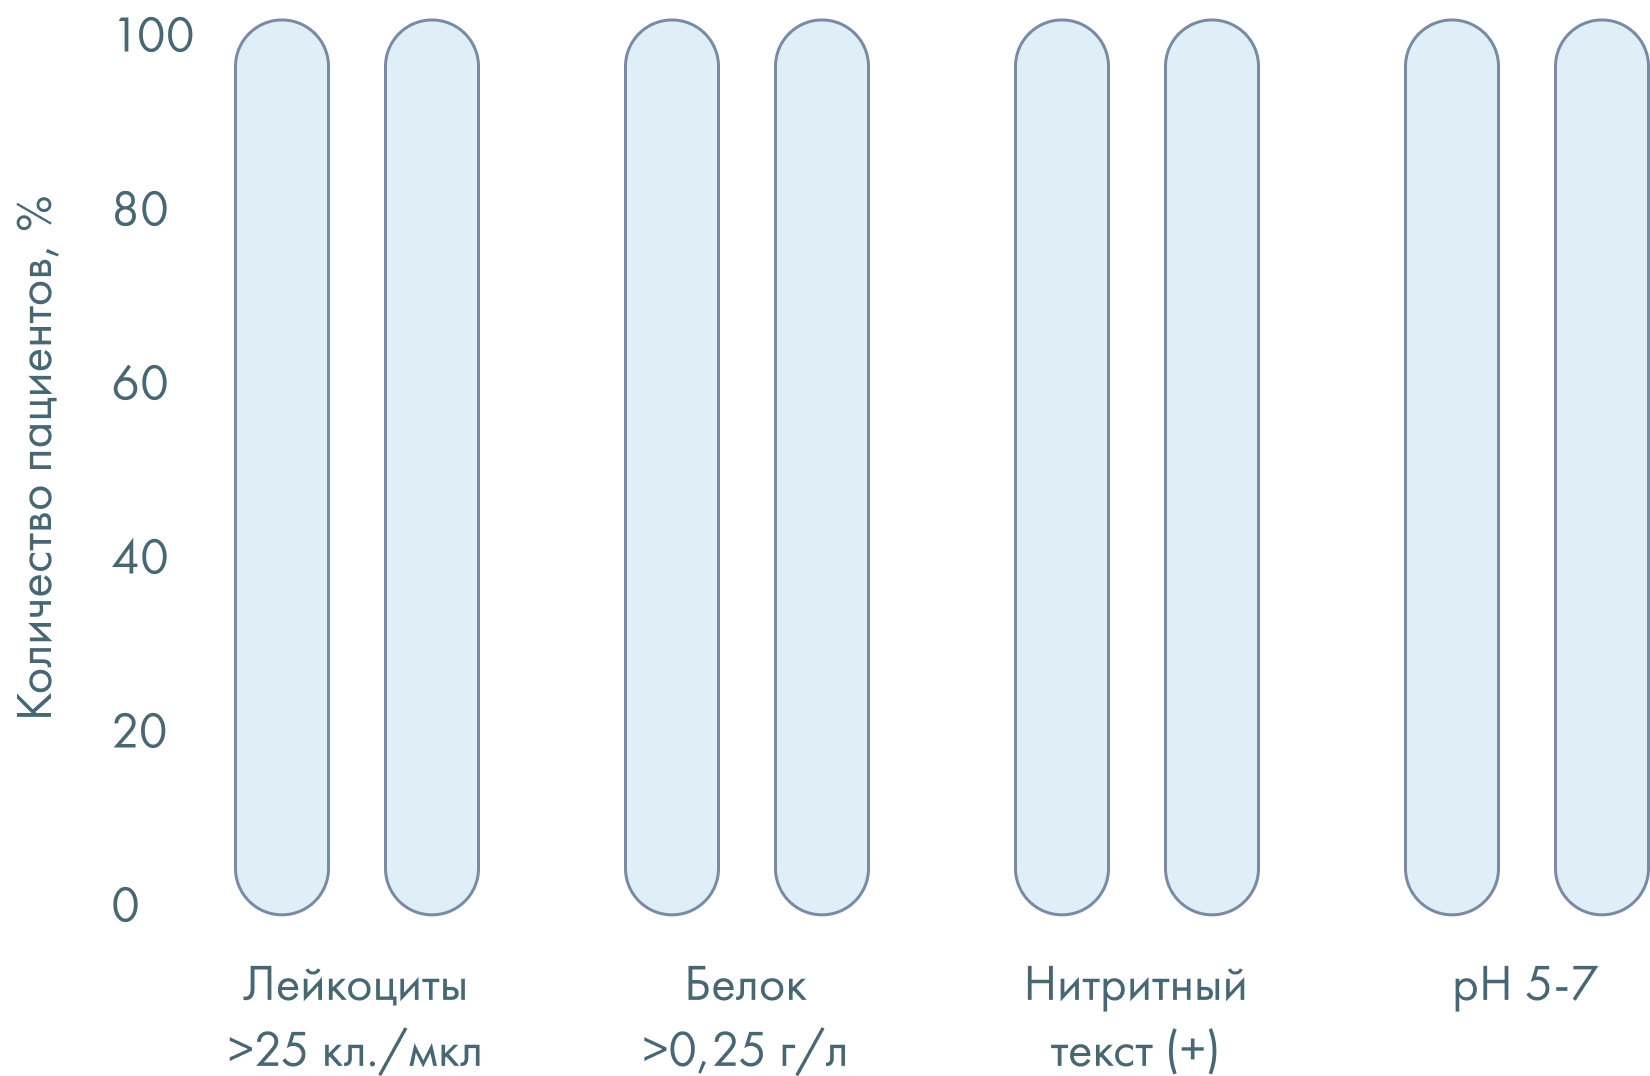

Диагностика1

- Анализ мочи (для старта эмпирического лечения).

- Бактериологическое исследование мочи с антибиотикограммой (при хронической ИМП — при каждом рецидиве). Показание к лечению: бактериурия ≥10³ КОЕ/мл в средней порции утренней мочи при самостоятельном мочеиспускании.

- При выделениях из влагалища: исследования pH для исключения бактериального вагиноза и гормональных нарушений в пери- и постменопаузе, биоценоза методом ПЦР на исключение ИППП.